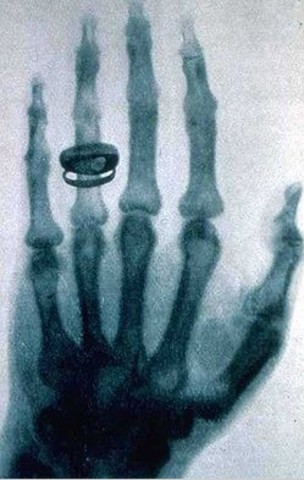

• rayos x

rayos x

Tesla empezó a investigar lo que después se llamó rayos X